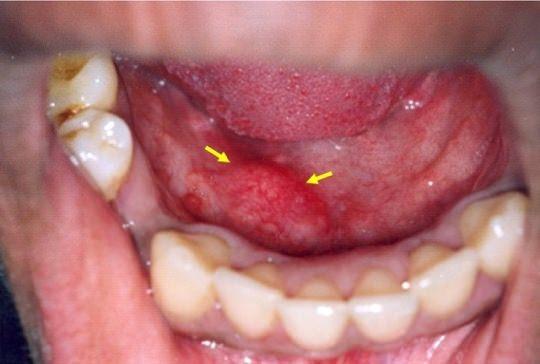

Dis Eti Kanseri Belirtileri Nelerdir Dislere Iyi Gelen Besinler Hangileridir Saglik Haberleri